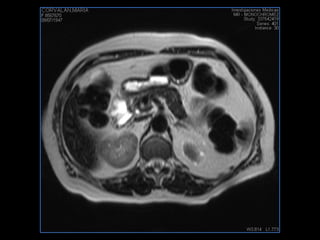

LIC ALEJANDRA GALVEZ RM DE ABDOMEN

PROTOCOLO abdomen COR T2, AXIAL supresion grasa AX T1 +SAG T2  CON   GADOLINIO :  COR T1+AX T1(DIN) SAT: NO  FASE: RL THK: 6MM  COIL:  GAP: (FACTOR 1.4) 2MM FOV: 40 CM NEX:2 SINCRONIZACION RESPIRATORIA EN 3 O 4 CICLOS ALE

resonancia de abdomen